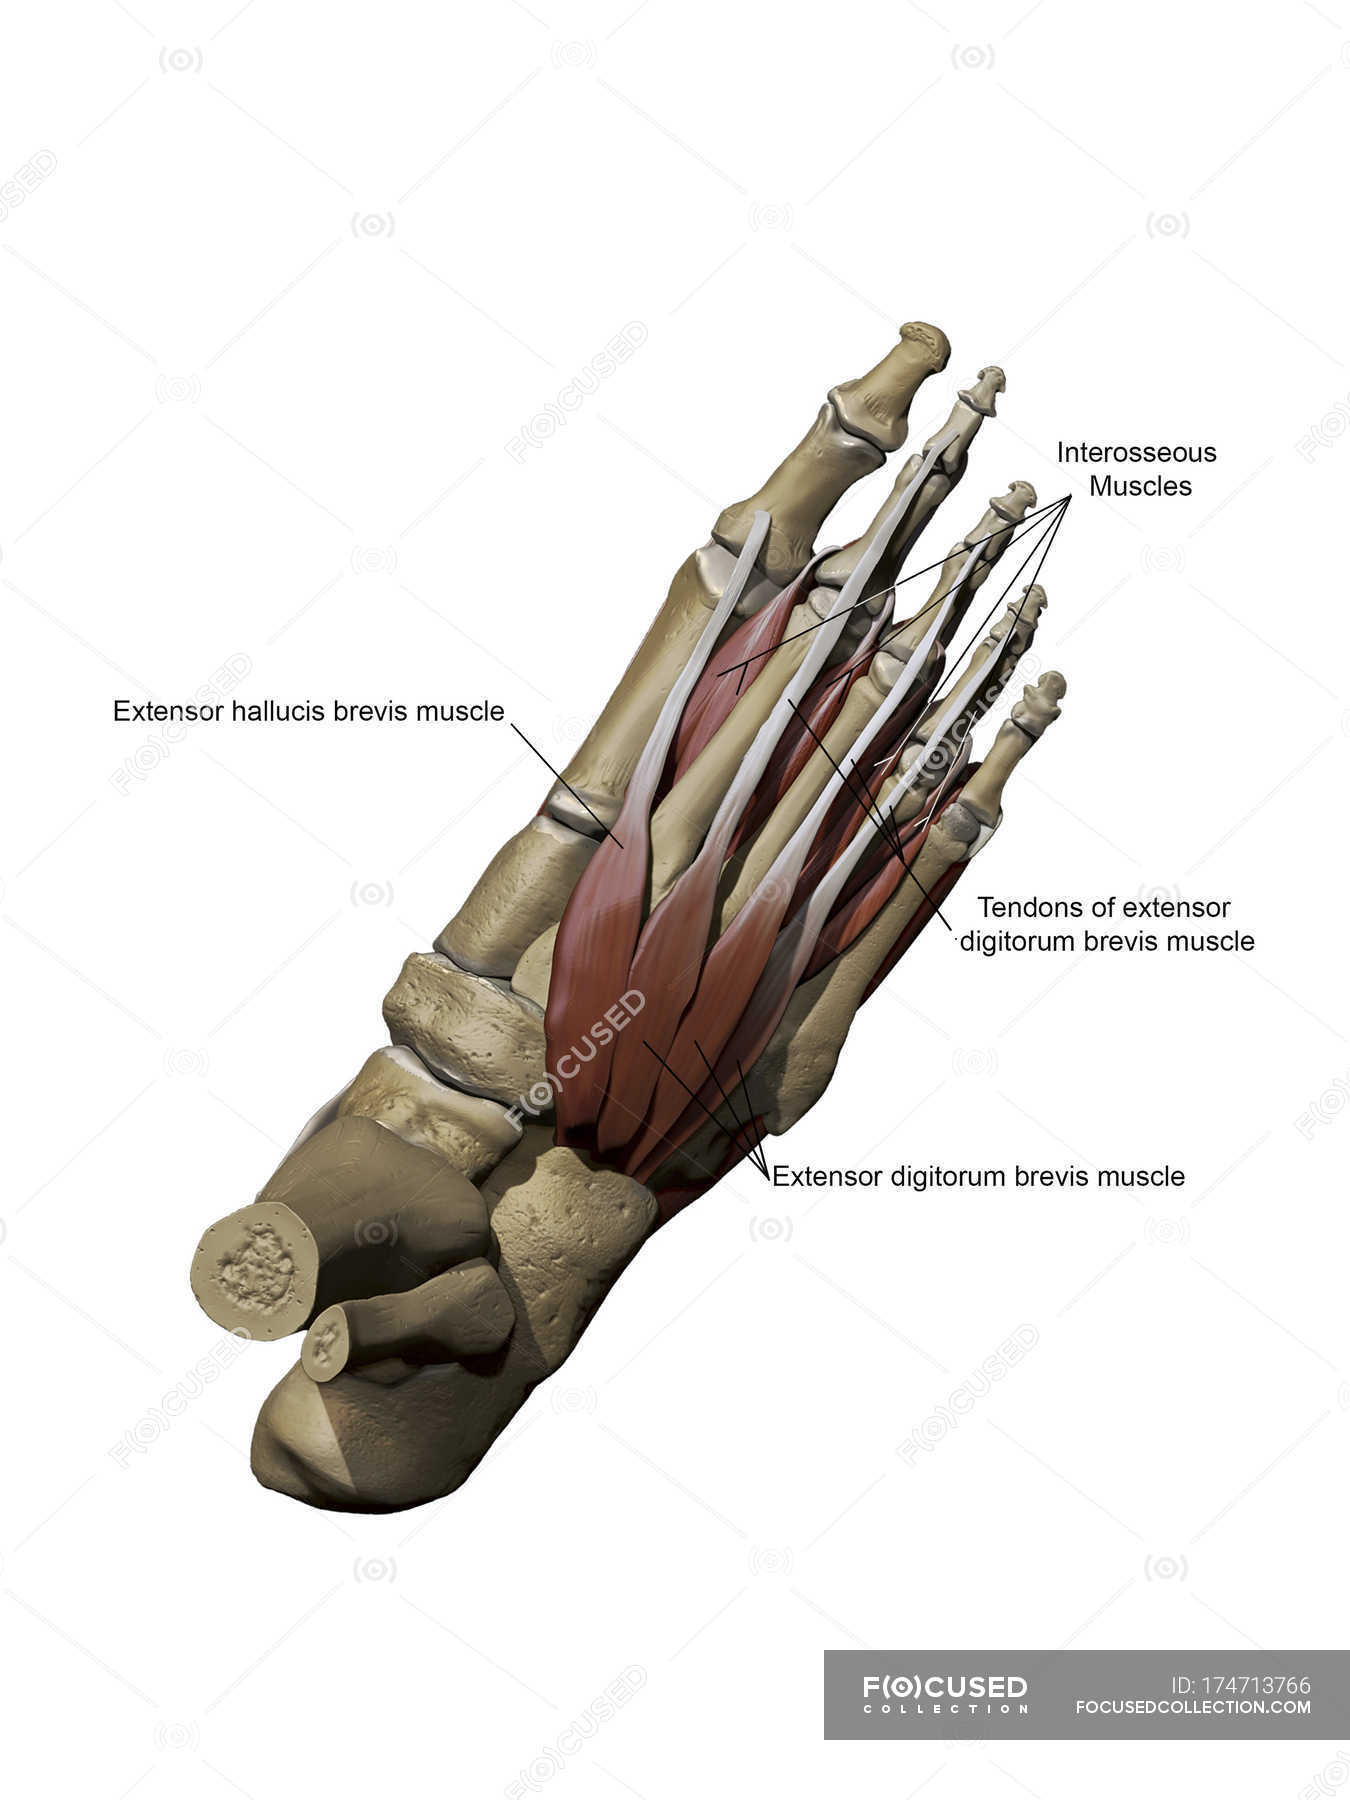

Muscolo Estensore Breve Delle Dita Del Piede (o Pedidio

www.pinterest.chpiede dita estensore muscolo legamenti breve collo muscoli medicinapertutti anatomia caviglia umano lungo tenosinovite dolore plantari muscolare scheletro salvato questi

www.pinterest.chpiede dita estensore muscolo legamenti breve collo muscoli medicinapertutti anatomia caviglia umano lungo tenosinovite dolore plantari muscolare scheletro salvato questi

Piede Con Muscoli Intermedi Dorsali E Strutture Ossee Con Annotazioni